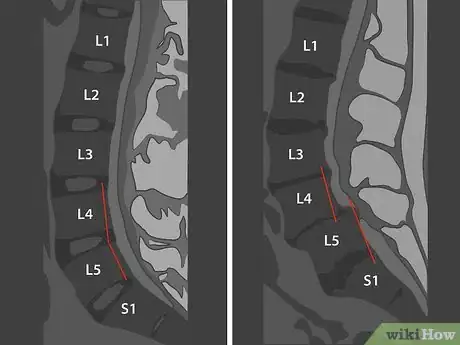

1Count the vertebrae of your lumbar spine. The vertebrae in your spine are divided into 5 regions. The lumbar region, consisting of 5 vertebrae, is the lowest region of your spine with movable vertebrae. In the 2 lower regions, the sacrum and the coccyx, the vertebrae are fused together.[6]

- The 5 vertebrae of your lumbar spine are numbered from 1 to 5, starting at the top and going down. You can count them down on your sagittal MRI.

- Medically, the vertebrae are labeled with an "L" indicating the lumbar region, followed by the number. For example, the second vertebra from the top of your lumbar spine is called "L2."

Tip: A sagittal image may also show the thoracic vertebrae above the lumbar section of your spine. To correctly identify the lumbar vertebrae, it may be easier to count up from the bottom.

4Draw a line down the vertebrae to check your alignment. Looking at the sagittal image, the edges of your vertebrae flowing down your spine should be even if you have normal alignment. If any of the vertebrae are protruding beyond the others, so that the line isn't smooth, this may be the cause of some of your symptoms.[13]

- Your spine has a natural curve at L4 and L5, so it won't be a straight line all the way down. However, the line you draw (including the curve) should still be smooth and even.